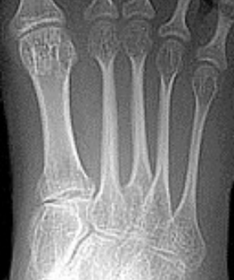

Describe the alignment of metatarsal 2 | There is no angulation nor displacement of the distal segment relative to the proximal segment. |

Describe the alignment of metatarsal 3 | The distal segment is displaced laterally (50% apposition) and angulated medially. |

Describe the alignment of metatarsal 4 | The distal segment is displaced laterally (75% apposition) but there is no apparent angulation. |

Describe the tubulation of the metatarsals | Metatarsals are overtubulated - decreased girth. |